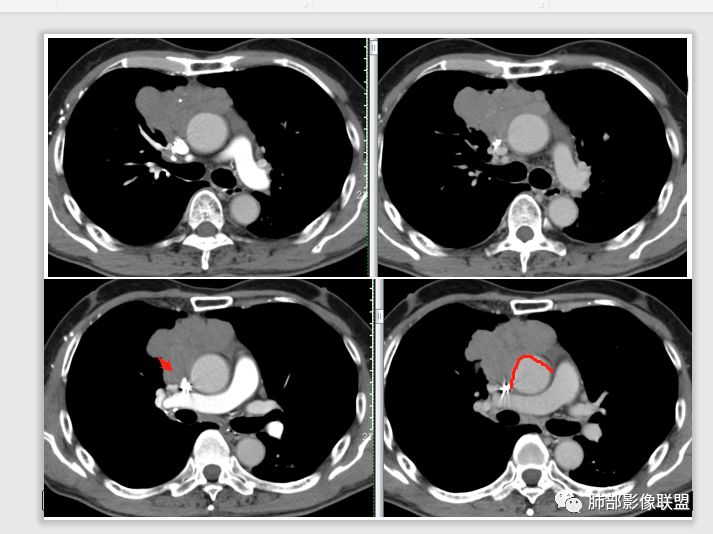

南边: 支持点:主体在纵隔、与肺分界清楚,与支气管、肺血管关系不密切

琦遇: 病灶与大血管脂肪间隙消失,也是提示不在肺内

南边: 从病灶与血管的关系看,骑跨在主动脉上,上腔静脉后移,病灶整体前朝后推,但是跨中线到对侧,主动脉偏移不明显,提示病灶前方来源,朝后推,如果侧方来源,朝对侧推移,支持前纵隔来源,然后就是性质?性质一般两个方向,有些有特征性征象,直接定病理可能比定良恶性更容易;有些特征性正想没有,但是可以提示良恶性,前纵隔肿瘤:胸腺、淋巴、(这年龄生殖类不太支持)

琦遇: 有分叶、有钙化、无坏死、有明显强化,不规则分叶,脂肪间隙模糊,与大血管分界不清,应该支持恶性多点吧,但是侵犯性不强

南边: 然后神经、脂肪,最多见的:胸腺的瘤、癌,其次淋巴瘤;然后才是其他,分叶明显,点状钙化,线样间隔,支持胸腺瘤吧,高度怀疑胸腺瘤